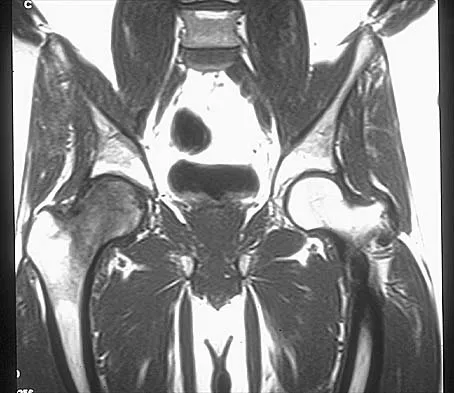

Figures 10a through 10c show the plain radiograph and MRI scans of a 41-year-old man who has right hip pain. What is the most likely diagnosis?

Explanation

Transient osteoporosis is a self-limited painful but reversible disorder. Although first described in pregnant women, it is more common in young to middle-aged men. The radiograph shows loss of mineralization in the right hip relative to the left side. There is no osseous destruction or cortical expansion typical of metastasis or giant cell tumor. The process is confined to the femoral side of the joint unlike rheumatoid arthritis, which would be centered in the joint. Osteonecrosis is better defined with sharp but irregularly shaped margins, and there is no double-line sign. The MRI scans reveal diffuse edema in the femoral head and neck that is atypical for osteonecrosis. Transient osteoporosis may recur in the same or opposite hip.